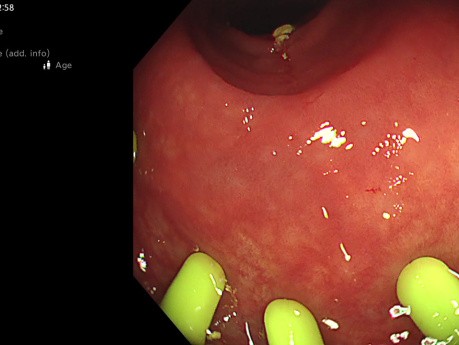

Melanosis Coli

La melanosis coli es una afección médica causada por la liberación de una molécula de pigmento, llamada lipofuscina, en las membranas mucosas del intestino grueso (colon). La melanosis coli no pone en...